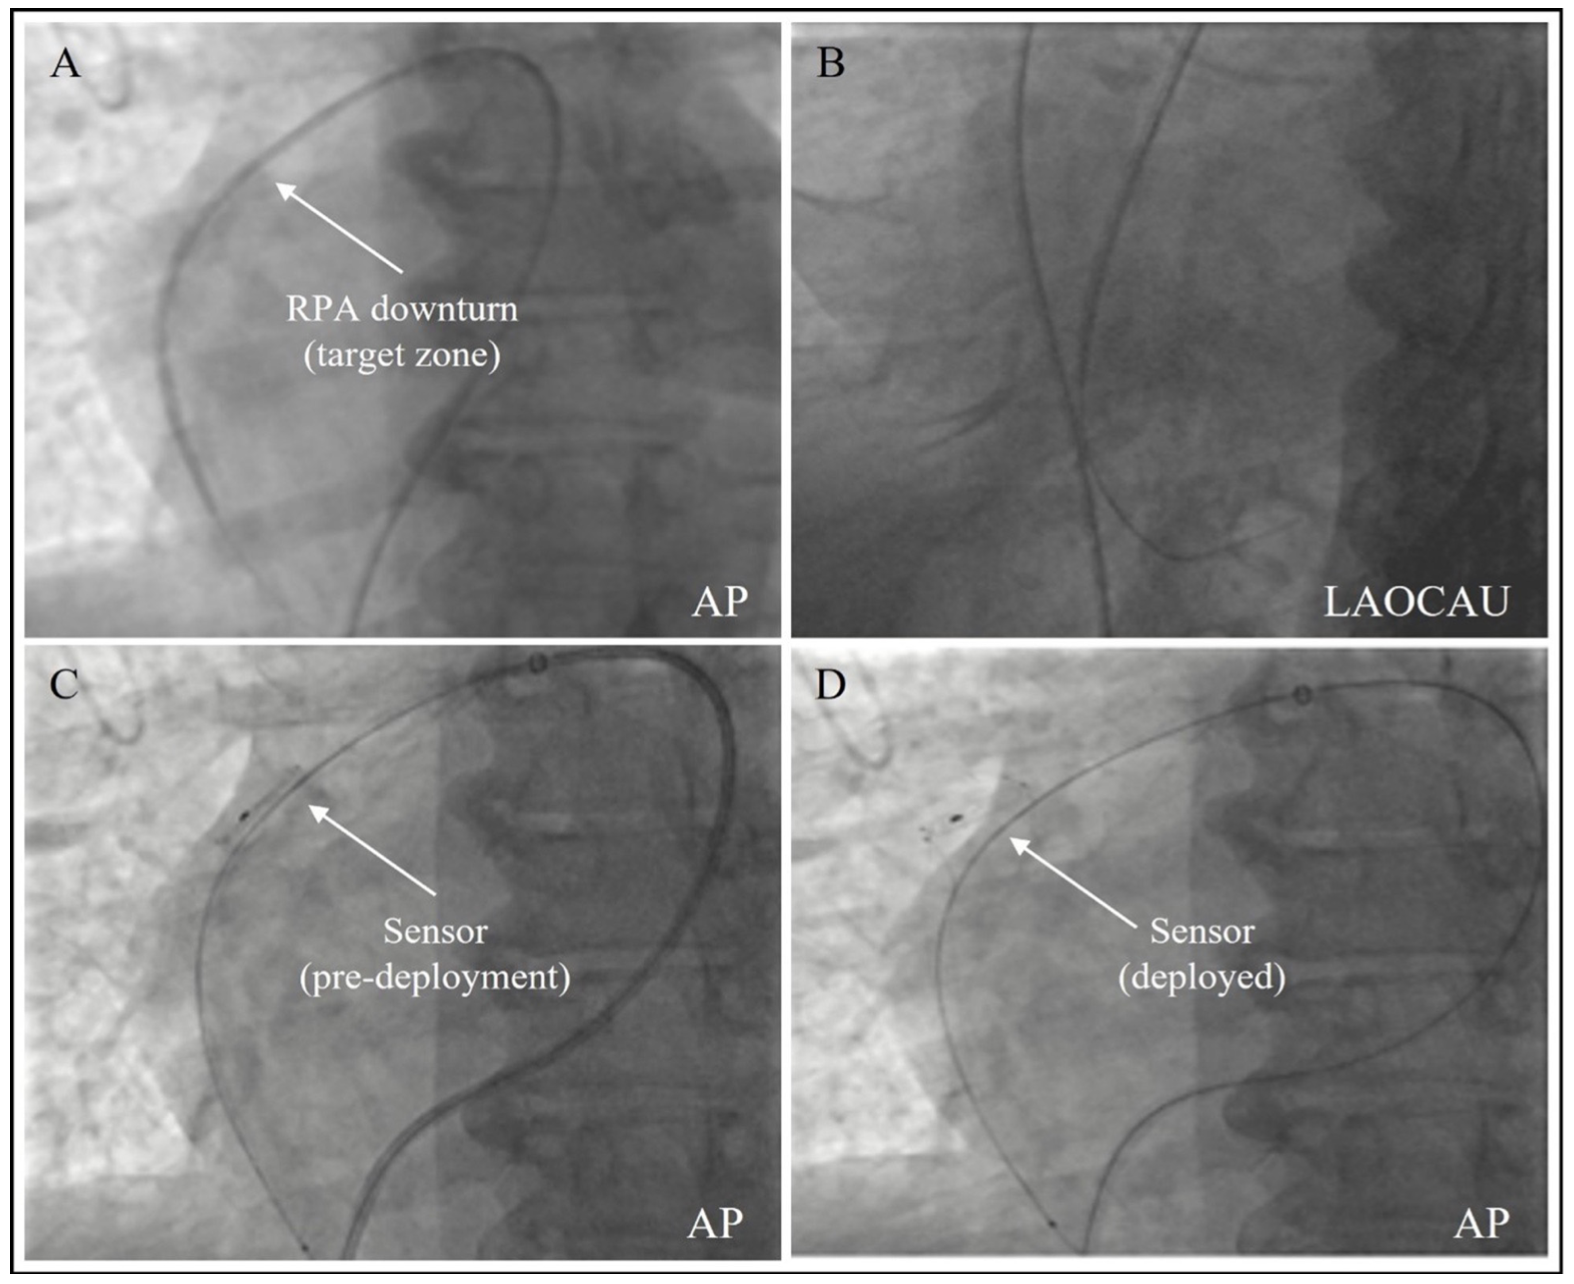

Pulmonary artery vessel mapping. The Cordella PA pressure sensor is implanted in the RPA in the target zone depicted in Figure 1. Using standard catheterization techniques, a Swan-Ganz PA catheter is first positioned at the RPA. In some cases, access to the RPA may be assisted by a guidewire. The target zone diameter must be between 12-26 mm. Quantification of this diameter can be done using quantitative vascular angiography (QVA), catheter features such as the PA catheter balloon size, or radiopaque catheters that allow dimensional estimation. Visualization of the RPA downturn may be achieved by 5-10 mL hand injection of contrast through the PA catheter. Otherwise, the PA catheter may be exchanged for larger catheters such as a pigtail or straight flush catheter and either hand or power injection may be used to visualize the RPA. It is important to ensure the tip of the catheter is proximal to the downturn of the RPA. Once the PA catheter is in position, pulmonary angiography is performed (typically, a hand injection through the PA catheter) in the antero-posterior (AP) and left anterior oblique (LAO) caudal views. Most importantly for optimal visualization, a maximal inspiratory breath hold is performed when obtaining the angiograms. Once the downturn is visualized on the AP view, the target zone is identified along with the posterior right pulmonary distal vessel. As the distal vessels may overlap, the AP and LAO caudal views assist in identifying the largest posterior distal vessel of the RPA. Generally, LAO 30° and caudal 30° are the preferred projections for optimal visualization.

Pulmonary artery guidewire placement. The guidewire (eg, Extra Stiff Amplatz 0.025˝) necessary for the delivery system is positioned in the right lower lobe branch of the RPA at the location of A8-A10 branches (largest posterior descending artery). In Figure 3, multiple catheters (eg, PAC, multipurpose, JR4, 3DRC, etc) may be used to obtain the adequate guidewire position in the A8-A10 branches based on the observed anatomy of the vessels. Ideally, the catheter used to visualize the vessel can be used to wire down the support wire. Other, more flexible, wires are also optional to gain access to the adequate distal vessel, which can then be exchanged to an Amplatz or other stiffer wire. If possible, the support wire should be positioned in the largest posterior vessel distal to the downturn (A8-A10). Use of breath hold for clearer images is recommended during PA access while comparing with the landmark angiography. Once distal access had been achieved with the guidewire in place, wire position should be checked in opposite views (ie, AP and LAO caudal) to confirm appropriate placement.

Sensor preparation and insertion. The delivery system is inspected on the sterile table for damage and the stylet is removed from the distal end. Then, the side port and the guidewire lumen are flushed with sterile saline and the handle is tested to ensure appropriate torque. The delivery system is threaded over the guidewire through the distal tip and inserted through the introducer. Once inserted, the Cordella sensor, attached to the delivery system, is advanced using fluoroscopic guidance over the guidewire through the right heart and positioned in the selected target zone of the RPA, taking care to avoid other medical devices (eg, pacemaker and defibrillator leads) that may be present. During this maneuver, if there is difficulty advancing the delivery system through the heart, one can retract the system 1-2 cm proximally and then apply torque to the handle to rotate the Cordella sensor such that it is on the inner curve of the pathway to the RPA. Once at the target zone, the torque handle should be used to turn the sensor into the anterior-facing orientation, as indicated by the radiopaque sensor marker dots for anterior deployment. Once in target deployment position (distal end of the sensor body at the right interlobar RPA downturn, anterior facing) the release wire cap is turned a quarter turn counterclockwise followed by slow pulling of the release wire cap, deploying the sensor. The release wire should then be pulled all the way out of the delivery system and discarded. Following sensor deployment (Figure 3B), the guidewire is pulled back into the tip of the torque catheter, the delivery system is pulled away from the sensor, and the torque luer is unscrewed to disconnect the luer to allow retrieval of the torque catheter and pulled 2 cm proximal. The wire is pushed inside the torque catheter (to prevent it from catching on the anchors) while the stability sheath should be kept in the pulmonary artery, held in position. Eventually the torque catheter is removed completely, keeping the stability sheath in the PA, proximal to the deployed sensor.

The right femoral vein was accessed with a 14-Fr introducer using modified Seldinger technique. RHC was performed with a 7.5-Fr Swan-Ganz catheter. The PA systolic pressure was 68 mm Hg with a mean PA pressure of 42 mm Hg and a mean pulmonary capillary wedge pressure of 18 mm Hg. A 0.025˝ Stiff Amplatz wire (Cook Medical) was positioned in the distal RPA, while doing deep breath holds to facilitate wire positioning. Adequate wire positioning in the A10 position was verified by the downturn shape of the wire in AP view and the downturn medial shape in 30° LAO, 30° caudal view (Figure 7A and Figure 7B).

The Cordella PA pressure sensor was then advanced over the wire proximal to the downturn of the RPA and 10 mL of hand injection via the side port of the Cordella stability catheter was enough to verify correct location of the sensor body prior to deployment of the anchors (Figure 7C). The sensor was successfully deployed (Figure 7D), the wire was withdrawn, and sensor calibration was performed through the stability sheath. Total case time was 61 minutes. Following sensor calibration after sensor deployment, the patient was able to ambulate immediately after the procedure and was discharged home the next day.